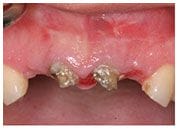

楊小姐年紀不大,但是從小因為蛀牙而做了很多假牙,又因為在鄉下沒有好的醫療環境,所以被假牙包覆住的牙齒早就腐壞,讓她很自卑,拜植牙之賜,楊小姐將一口壞牙換成漂亮又不怕蛀牙的植牙,現在她終於有自信開懷大笑。

植牙過程

治療前